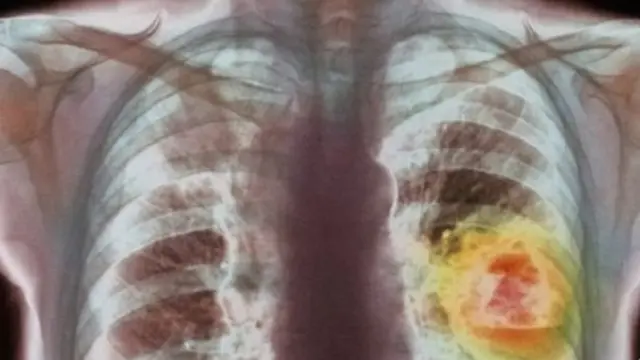

Butiran-butiran emas kecil dapat digunakan dalam perang melawan kanker, ungkap sebuah penelitian terbaru.

Ilmuwan di Universitas Edinburgh menemukan bahwa logam mulia tersebut meningkatkan efektivitas obat yang digunakan untuk mengobati sel kanker paru-paru.

Kanker yang sulit diobati